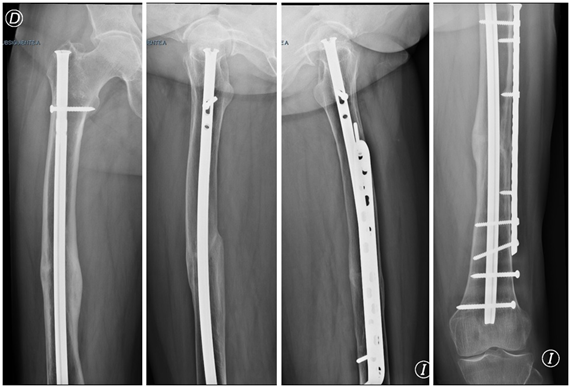

After the fall the patient is admitted and the closed fracture of both femurs in the diaphyseal region is verified, the fracture line was oblique short and with a medial spicule (Figure 2). Because of the characteristics of the radiographs and the anamnesis, we could verify that the patient presented 5 major criteria and 5 minor criteria for the diagnosis of FFA. The hemodynamic status was not compromised and presented no other problem.

Figure 2 X-rays on admission. The characteristics of FFA are observed. A) Femur Der. B) Femur Left.

The patient was admitted to the common room and bilateral trans-tibial skeletal traction was performed. The reduction and osteosynthesis was performed on the same day of the accident, the patient was operated on a traction table and the osteosynthesis was performed on both femurs with milled intramedullary nails (Synthes universal nail). Osteosynthesis was performed first of the left femur and then the right one (Figure 3). Immediate partial load was indicated with the use of crutches. The use of alendronate was discontinued, it was indicated to continue with vitamin D and no other medication was added.

Figure 3 Immediate post-surgical radiographs.